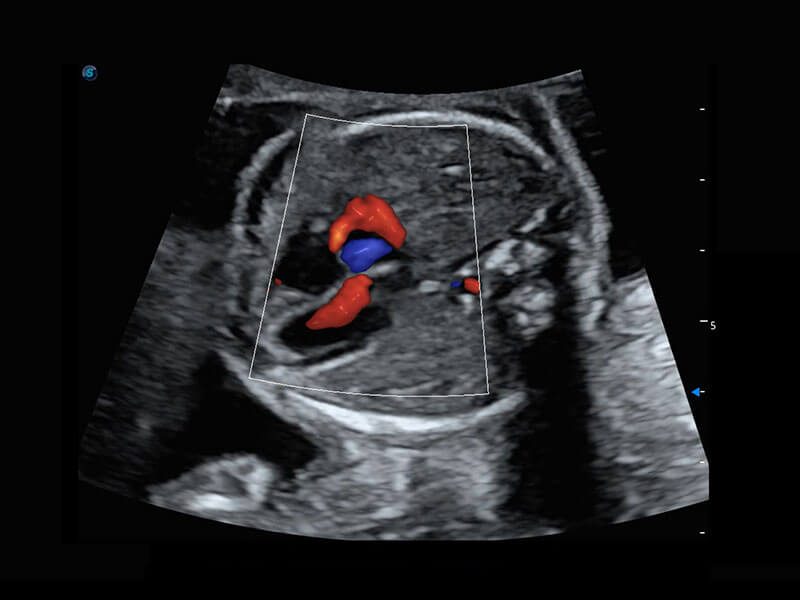

胎心筛查

P60搭载一系列胎儿心脏成像技术,实现精细的胎儿心脏评估。

• 右室双出口